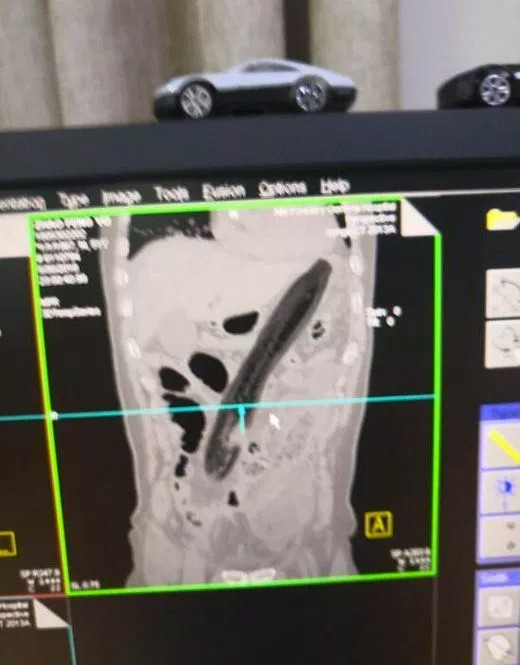

Çin, son yılların en şaşırtıcı tıbbi olayını konuşuyor. Çin'de ismi açıklanmayan hasta geçtiğimiz hafta mide bulantısı ve karın ağrısı şikayetiyle hastaneye gitti. Röntgeni çekilen adamın anüsünden 30 santimetrelik patlıcan çıktı.

HASTALIĞI İÇİN YAPMIŞ; Yapılan incelemeler ve röntgen sonuçlarına bakarak adama soru soran doktorlar aldıkları yanıtla iyice şaşkına döndü. Acı içinde kıvranan adam sindirim ve boşaltım sorununu ortaya kaldırmak için anüsünden 30 santimetre uzunluğundaki bir patlıcan soktuğunu ve bunun 2 gündür içinde sıkıştığını söyledi.

Şok içindeki doktorlar adama derhal müdahale ederken yapılan operasyon sonrasında adamın sağlık durumunun düzeldiğini açıkladı. Patlıcan aracılığıyla kolonu genişletmeye çalıştığını söyleyen adamın, bu tedavi yöntemini büyüklerinden öğrendiğini söyledi.